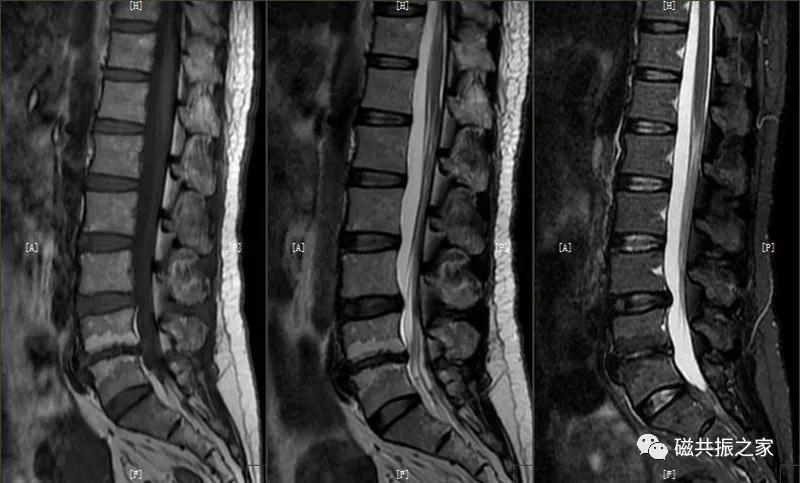

10.椎体肿瘤

椎体常见的肿瘤为转移瘤

椎体转移瘤T1WI常表现为低信号,T2WI为高/中/低信号,脂肪抑制为高信号,常累及附件。

疑是血液系统疾病引起的腰椎异常信号改变,部分炎性病变可引起该表现。